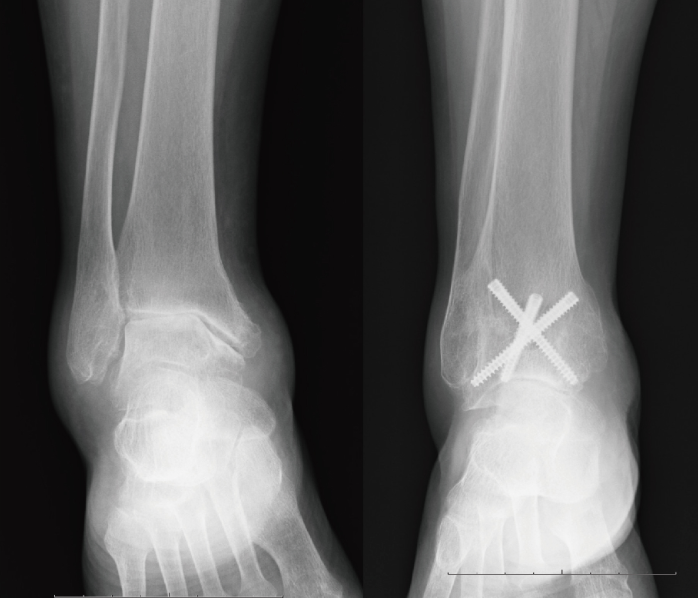

↓鏡視下関節固定術